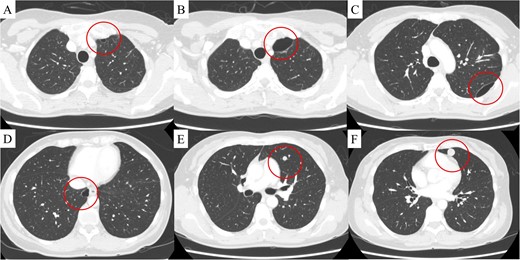

The patient was a 54-year-old woman with no history of smoking. Three years prior to being referred to our department, the patient had undergone total abdominal hysterectomy and bilateral salpingo-oophorectomy for a uterine STUMP. Six months thereafter, a single pulmonary nodule appeared in the left upper lobe (Fig. 1) and pulmonary metastasectomy was performed followed by four courses of gemcitabine-docetaxel therapy. One year thereafter, a single bulla was observed in the left lung (Fig. 2A). Subsequently, several bullae appeared and gradually developed (Fig. 2B–D); at referral, two additional pulmonary metastases were observed in the left lung (Fig. 2E and F). Because no other metastases were present, curative resection of the pulmonary metastases was planned. Additionally, we planned a bullectomy due to the lack of a reasonable explanation for bullae formation.

(A) Computed tomography revealed a bulla in the left upper lobe 1.5 years after uterine surgery. At 3 years, in addition to the development of the bulla in the left upper lobe (B), two more bullae appeared and gradually developed in the left (C) and right lower (D) lobes, and two pulmonary metastases appeared in the left lingular segment (E, F). The findings are indicated by circles.